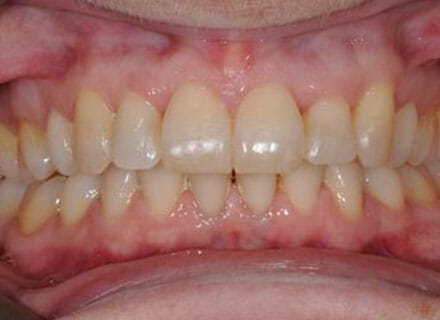

In this case, we needed to reduce the size of the central incisors as they were just too big. This combined with the crowding at the front had caused the lateral incisors to become trapped inside, pushing the big central incisor teeth forwards even more. After reducing the big teeth to a normal size we started with fixed clear bracket brace treatment and were able to complete this case in a little over a year.